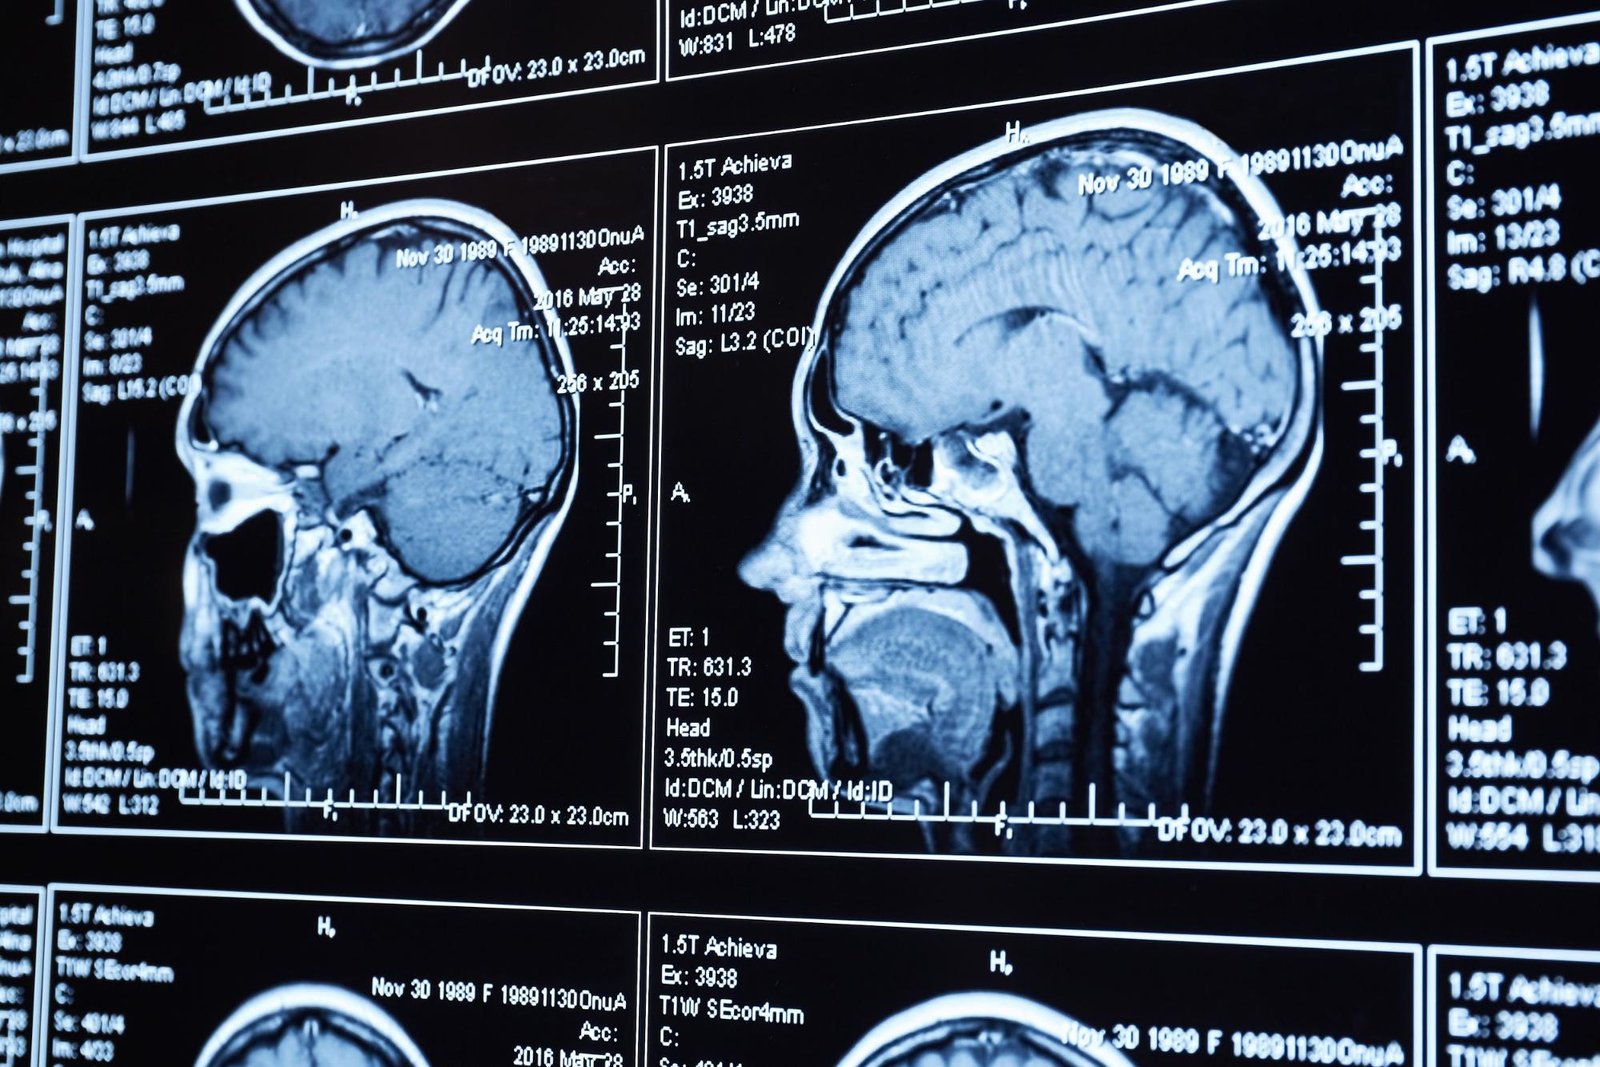

Diagnosis and treatment of a simple skull fracture usually involves a trip to the emergency room or urgent care center, X-rays and possibly a CT scan, and one or two follow-up visits with a neurologist. This can put medical costs at $3,000 to $5,000. Assuming another $2,000 for lost wages, that’s a total of $6,000 in economic damages.

First, gather your treatment records. You’ll need medical bills and other documents showing your prognosis. This includes the results of tests and procedures showing the precise nature of your injury. Records showing the necessity for surgery, rehabilitation, or other treatment are also important.